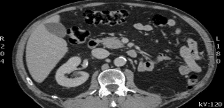

La tomografia computerizzata (TC o CT, dall’inglese Computed tomography, o TAC, Tomografia assiale computerizzata) è una tecnica radiologica con la quale si ottengono immagini di sezioni del corpo umano, evitando le sovrapposizioni delle diverse strutture più generalmente utilizzate nella radiologia tradizionale.

La tecnica si fonda sulla ricostruzione, operata da un calcolatore, della densità dei diversi tessuti del corpo umano, attraversati da un fascio di radiazioni X. Lo scanner TC è costituito essenzialmente da un tubo a raggi X e da rivelatori.

Il tubo radiogeno produce un fascio di raggi X che passa attraverso il paziente. Questo fascio viene catturato dai rivelatori e ricostruito per creare un’immagine di valore diagnostico.

La TC è caratterizzata da una elevata risoluzione di contrasto; tuttavia, può risultare difficile distinguere il fegato dalle strutture vascolari in esso contenute. Per ovviare a questo problema, si ricorre all’iniezione di un mezzo di contrasto, a base di iodio e, solitamente, iniettate per via venosa.

Il paziente si sdraia su un tavolo comandato da una consolle centrale di controllo. La regione corporea viene posta all’interno dell’apparecchio TC munito di una ampia apertura. Le immagini vengono acquisite in pochi secondi e al paziente viene chiesto di rimanere immobile e di non respirare nel caso di esami del torace e dell’addome.

L’esame TC trova impiego in tutti gli ambiti. In base alla tipologia di esame da effettuare e/o sulla base del quesito clinico, può essere eseguito con somministrazione di mezzo di contrasto.

Tac Addome Completo, a cosa serve e come si esegue: L’esame TAC Addome Completo (superiore e inferiore) è lo studio degli organi e dei vasi

Uro TAC, a cosa serve? Tac Uro è l’esame che consente lo studio delle vie urinarie (reni, ureteri, vescica), dopo iniezione del mezzo di contrasto